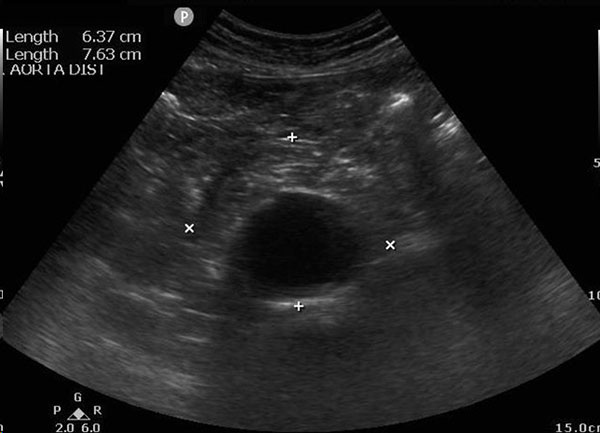

Abdominal aortic aneurysm (AAA) is a disease that primarily affects older adults. The aorta is made of three layers. The adventitia is a thin outer layer that surrounds the media, the thick central layer. The intima is the innermost layer. The media is comprised of layers of smooth muscle cells and elastic fibers known as the elastic lamellae.87 Degeneration of this layer leads to the formation of an AAA. An aneurysm was defined by the Society for Vascular Surgery and the North American Chapter of the International Society for Cardiovascular Surgery in 1991 as a permanent localized dilation of an artery that is at least 50% larger than the expected normal diameter.88 An AAA usually is defined as having a diameter of 3.0 cm or larger.89 (See Figure 1.)

Figure 1. Abdominal Aortic Aneurysm |

Transverse ultrasound image showing abdominal aortic aneurysm with intraluminal thrombus |

Image used with permission from Dr. Alexis Salerno. |